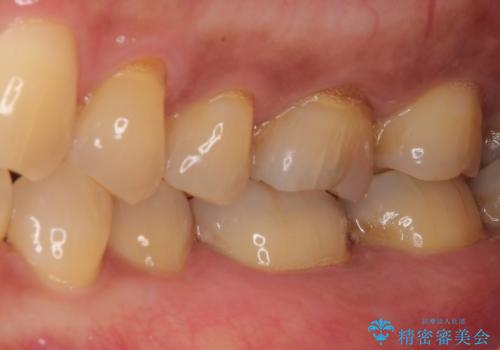

- 銀歯の周りに物が挟まるとのことで来院された患者様です。

咬合力が強く、銀歯周りの歯質に隙間が生じてむし歯になっている状態でした。

むし歯をしっかりと取り除き、強い咬合力を考慮してゴールドインレーにて修復することとしました。